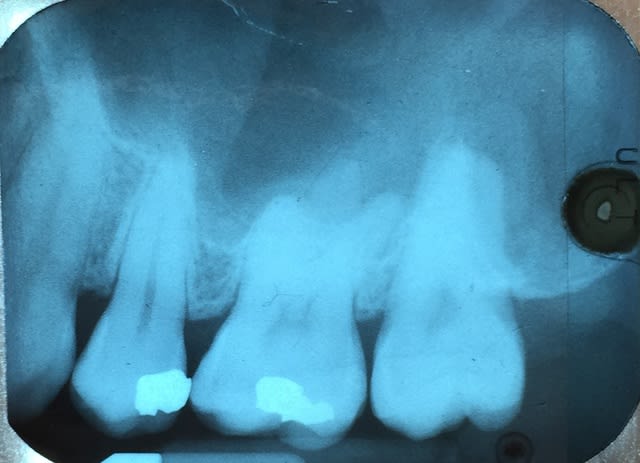

Bonjour, j'ai eu une nouvelle patiente (28 ans) tout à l'heure qui se présente en ayant une gène à la mastication sur le secteur molaire maxillaire gauche (uniquement en mangeant)

Compte tenu de la radio et de l'élargissement desmondontal au niveau de la 25 et 26, je suspecte plutôt une prématurité, mais bon j'en suis pas sur du tout.